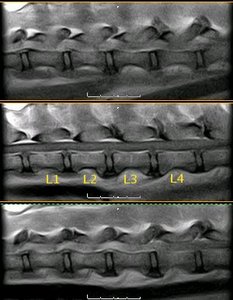

Radiografía laterolateral de la columna vertebral lumbar canina |

Radiografía ventrodorsal de la columna vertebral lumbar canina |